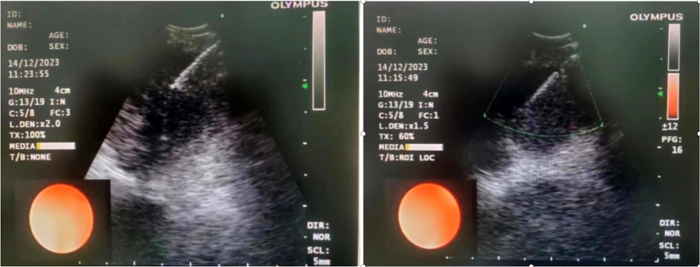

病例1

患者,女,72歲,2月來“反復咳嗽、咳痰,偶咳白痰中帶血絲”,胸部CT提示“肺占位、肺炎”,收住院。完善胸部強化CT提示“左肺占位、肺炎、縱膈多發(fā)淋巴結腫大”,電子支氣管鏡檢查見左肺上葉支氣管血塊及壞死物阻塞,清除后見管腔通暢,刷檢DNA細胞學示“細胞退變明顯,建議進一步檢查”。10月27日行CT引導下肺穿刺活檢,病理示“機化性肺炎”,給予抗感染及激素治療,患者癥狀好轉出院。半月前,患者復查肺CT發(fā)現(xiàn)病灶較前稍有增大,張強主任考慮患者癥狀雖有好轉,但仍存在腫瘤性病變可能性。經(jīng)過討論及與患者家屬充分溝通后,決定實施支氣管內超聲引導下針吸活檢術(EBUS-TBNA)+電子支氣管鏡檢查+現(xiàn)場快速評價(ROSE)技術,以提高診斷陽性率。術中ROSE提示查找到可疑癌細胞,取材量較足分。最后病理檢查明確診斷為低分化肺腺癌,隨后進行基因檢測,明確了治療方向。